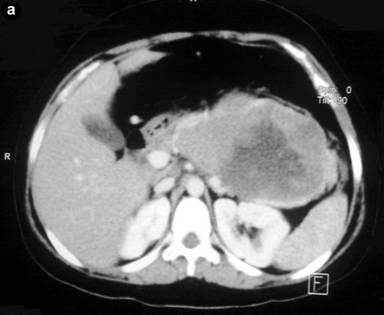

A 18-year old-female presented with progressively increasing mass in the left hypochondrium and epigastric regions of 6 months duration. There was no history of jaundice, vomiting, change in stool color, diarrhea, or flushing. On examination there was a painless, firm mass occupying the epigastric, left hypochondrium, umbilical regions which did not move with respiration. Laboratory investigations were normal, with normal serum level of CEA. Imaging in the form of ultrasonography revealed a large complex mass in the left retroperitoneum measuring 17x22x7 cm. Contrast enhanced multislice CT scan showed a large well defined mass of 17x24 cm with areas of degeneration, involving the region of the body and tail of pancreas, extending upward to the retrogastric space and downward to the level of aortic bifurcation, with no evidence of metastasis, with criteria suggestive for a solid and cystic papillary neoplasm of the pancreas (Figure 1).

Figure 1. Abdominal CT scan shows a large, well-demarcated, heterogeneous pancreatic mass. |